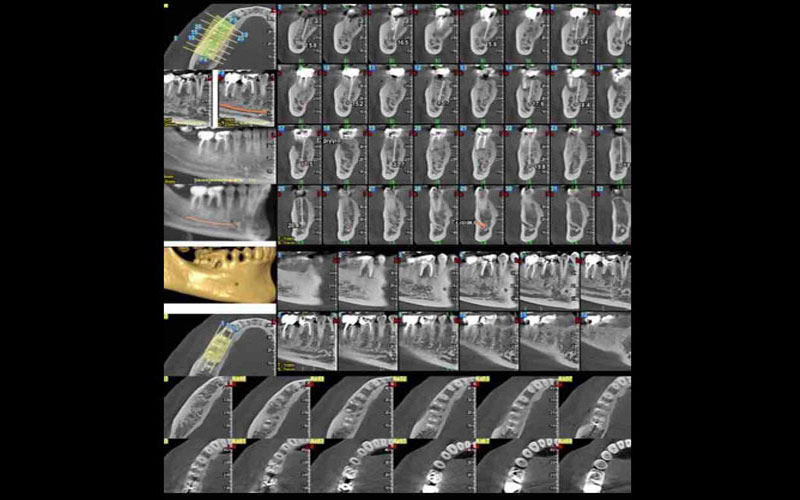

ΝΕΕΣ ΤΕΧΝΙΚΕΣ - COMPUTER GUIDED SYRGERY (DSD, PRP)

Στην εποχή των ραγδαίων εξελίξεων όσον αφορά χειρουργικές τεχνικές και υλικά, θεωρείται πλέον δεδομένο ότι τα οδοντικά εμφυτεύματα ,που αντικαθιστούν τη ρίζα του φυσικο...